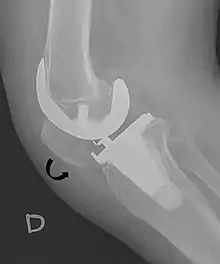

4. Melloni, Pietro; Veintemillas, Maite; Marin, Anna; Valls, Rafael (2013). "Imaging Patellar Complications After Knee Arthroplasty". Arthroplasty - Update. doi:10.5772/53666. ISBN 978-953-51-0995-2. (CC-BY-3.0)